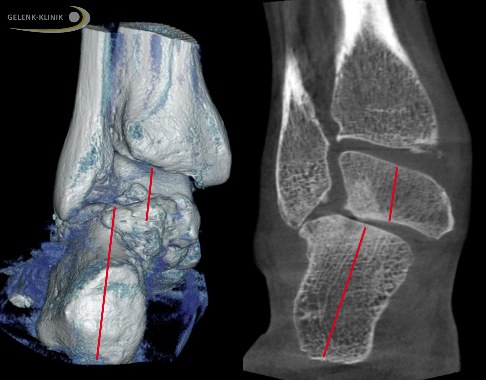

Verschiebungsoperation des Fersenbeins

Die knöcherne Verschiebung des Fersenbeins (Mediale Displacement Osteotomy, MDO) ist geeignet, die Fehlstellung des Rückfußes auszugleichen und korrigiert vor allem die Knickfuß-Komponente. Durch die Verlagerung des Fersenbeins nach innen verändert sich auch die Zugrichtung der kräftigen Achillessehne. Dies richtet den Fuß insgesamt auf.

Die Fehlstellung des Fersenbeins verändert die Zugwirkung der starken Achillessehne: Sie wird beim Gehen nicht ausreichend gedehnt und verkürzt sich daraufhin. Diese Verkürzung spielt eine wichtige Rolle beim Aufrechterhalten der Knick-Senkfußfehlstellung. Eine Normalisierung der Fersenstellung verhindert die fortschreitende Verkürzung der Achillessehne.